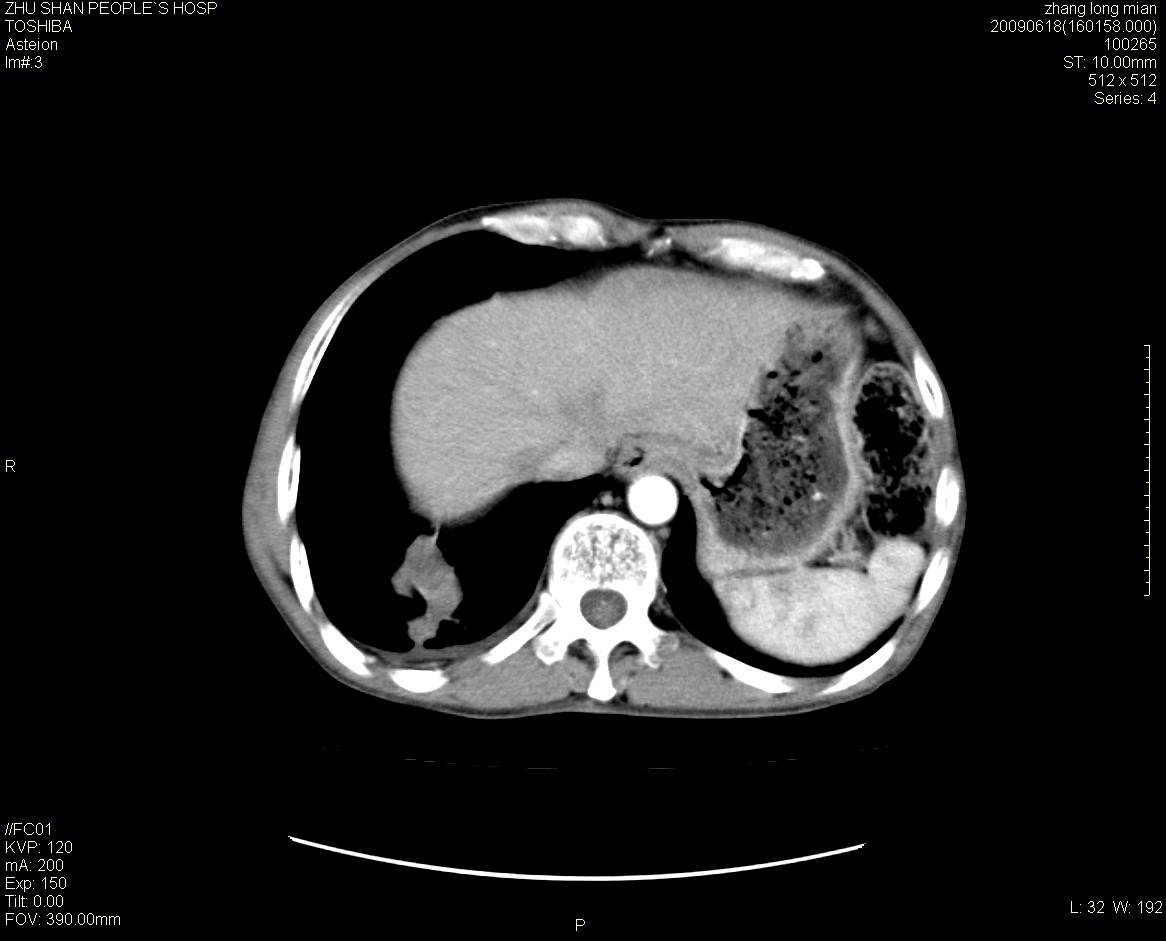

男性 65岁 胸片发现右下肺包块.诊断肺ca并纵隔转移没有问题吧!

两侧胸廓不对称,右侧呈塌陷改变,右肺萎缩。

右下肺见浅分叶状软组织块影,边缘有毛刺,其下部似见不完整偏心空洞影,邻近胸膜凹陷征,并胸腔积液。

增强见纵隔区气管隆突上下及左肺门区肿大淋巴结。左肺感染性病灶。

另见右上肺见一枚小结节影,性质待定。